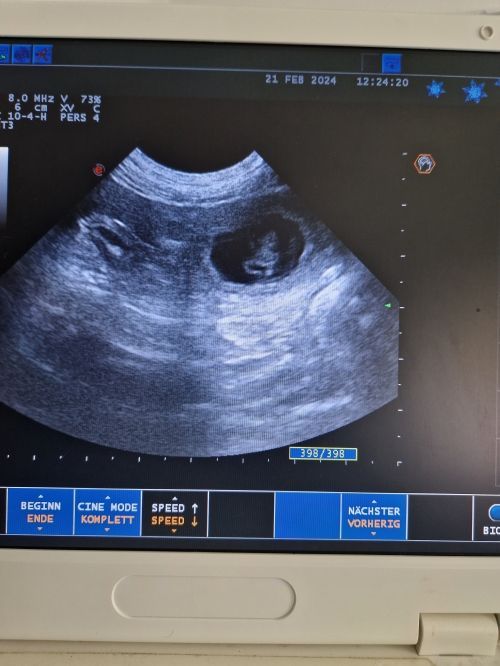

Tag 27 nach dem ersten Kontakt mit Ray dann die Überraschung, auf dem Bildschirm vom Ultraschallgerät können wir ganz deutlich kleine Fruchtblasen und am allerbesten: Kleine klopfende Herzchen ♥️ sehen.

Das Wunder hat begonnen: Unsere Cooki wird Mama🥰🥰🥰